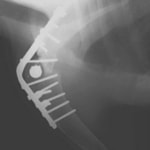

症例:柴犬 3歳

左後肢の完全挙上を主訴に来院されました。触診にて近位足根関節の過伸展を、レントゲン検査にて左足根関節周囲の軟部組織の腫脹、ストレス撮影によって距骨・踵骨と第4足根骨・中心足根骨間の脱臼および過伸展を認めました。

術中において、浅趾屈筋腱を剥離、内方へ牽引し、直接踵骨から第4足根骨までピンを挿入し(あらかじめ細いピンで下穴をあけておくとよい)、テンションバンドワイヤー法を併用し、関節軟骨の掻爬と海綿骨移植を実施しました。

術後レントゲン画像上に癒合が認められるまで約2ヵ月間は、運動を制限する必要があります。